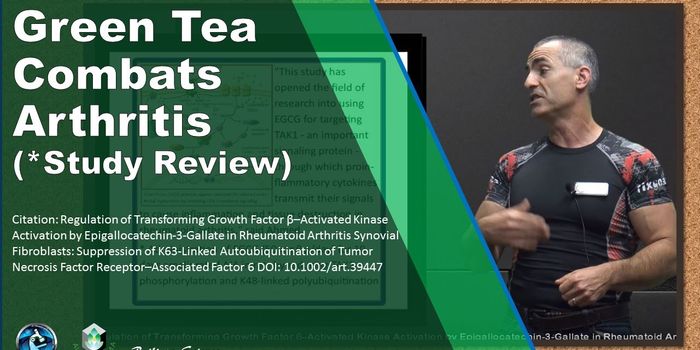

DEC 28, 2017VideosRheumatoid arthritis (RA) is much more common in women than it is in men, so research has traditionally focused on women ...